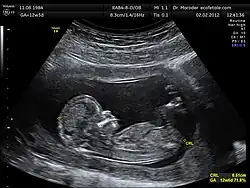

Ultrasonics deals with sound waves in solids, liquids and gases at frequencies too high to be heard by the average person. Specialist areas include medical ultrasonics (including medical ultrasonography), sonochemistry, nondestructive testing, material characterisation and underwater acoustics (sonar).[23]